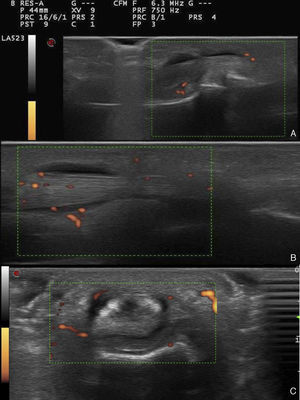

Presentamos el caso de un varón de 37 años de edad, afecto de una APs de inicio cutáneo en 2003, y con posterior afectación articular, en remisión clínica mediante metotrexate desde 2014. En el último control presenta un empeoramiento cutáneo y asocia dolor de características mecánicas a nivel de cuarto dedo de la mano derecha. La exploración clínica fue anodina, mientras que, la ecográfica muestra una tenosinovitis aguda del tendón flexor del cuarto dedo de la mano derecha, en toda su extensión volar (fig. 1). La clínica remite tras una infiltración corticoidea guiada mediante ecografía.

El presente trabajo pretende reflejar la importancia de la ecografía, no solo en el manejo de la AR, sino también en la monitorización y seguimiento de la APs en remisión clínica, y mostrar el control ecográfico de estos pacientes. Señalar que, la tenosinovitis aguda del tendón flexor de la mano, a menudo pasa desapercibida, y tal vez sea una manifestación presente más habitual de lo descrito en pacientes con una enfermedad de baja actividad inflamatoria6.